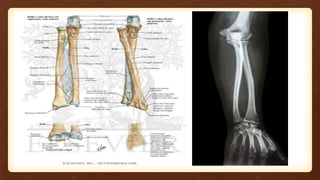

O documento discute a densitometria óssea do antebraço, recomendando mensurar o antebraço dominante devido apresentar maior densidade óssea. Aponta que aparelhos podem se referir à mesma região do antebraço por nomenclaturas diferentes, levando a aquisições e análises incorretas.